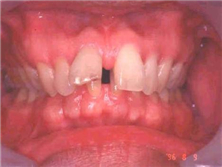

深覆合是一種上下頜牙弓的垂直關(guān)系的異常。指的是上前牙切緣蓋過下前牙牙冠長度1/3者或下前牙咬合于上前牙舌側(cè)1/3以上者。

• 有什么典型癥狀?創(chuàng)傷、唇外翻、下頜后縮